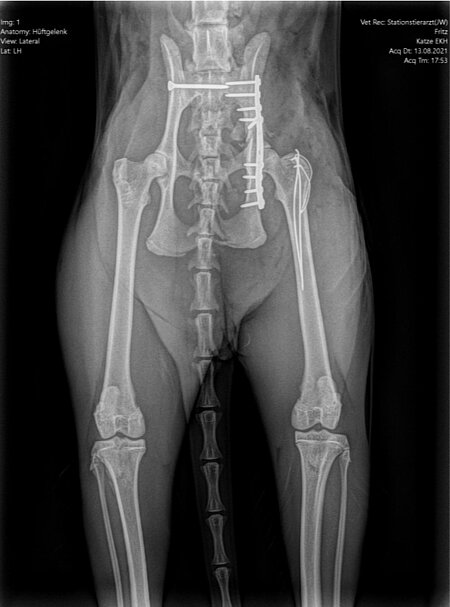

Am 13. August, also fünf Tage nach dem Unfall, entschied man sich dann zur Operation, da die Verlaufsuntersuchung dank der wiedergewonnenen Reaktionsfähigkeit des Patienten jetzt den Verdacht einer begleitenden Verletzung des rechten Ischias Nerven aufkommen ließ. Durch Vorbiegen einer Knochenplatte an einem Beckenmodell wurde der Eingriff sorgfältig vorbereitet, um die Operationszeit möglichst kurz halten zu können.

Zuerst wurden das ausgerenkte rechte Kreuz-Darmbein-Gelenk sowie der in seiner unmittelbaren Nachbarschaft verlaufende Ischias dargestellt und das Darmbein nach seiner Reposition mit einer 2,0 mm dicken und 24 mm langen Schraube an den Kreuzbeinkörper fixiert. Nach dem Wundverschluss wurde der Kater auf die andere Körperseite gelagert und sodann der direkt vor der Hüftgelenkspfanne Eine weitere Schraube diente der Adaptation eines Darmbeinsplitters an die Hauptfragmente. Da die Freilegung dieser Beckenregion meistens auch einen Knochenschnitt am Oberschenkel zum Verlagern der Kruppenmuskeln erfordert, wurden die Endsehnen dieser Muskeln mit dem knöchernen Segment abschließend durch 2 Bohrdrähte und einer 8-förmigen Drahtschlinge wiederbefestigt.

Röntgenbilder mit freundlicher Genehmigung Tierklinik Weilheim.

Sieben Tage nach der Einlieferung in die Klinik und drei Tage nach der Operation konnte Fritz bei gutem Allgemeinbefinden nach Hause entlassen werden.

Zu diesem Zeitpunkt war er in der Lage, selbstständig zu stehen. Die Ausfallerscheinungen des Ischias hatten sich durch das Einrenken des rechten Kreuz-Darmbein-Gelenks bereits gebessert. Auch die Stellreaktionen des rechten Vorderbeins, das nach den Röntgenbildern eine Prellung, aber keine Knochenverletzung erlitten hatte, waren schon wieder fast normal. Noch deutlicher waren die neurologischen Fortschritte beim Entfernen der Hautfäden eine Woche später. Trotz der positiven Entwicklung musste jedoch zur Ruhighaltung des Patienten für mindestens sechs Wochen geraten werden, damit alle Verletzungen des Beckenrings, auch die nicht fixierten Frakturen des Beckenbodens, heilen konnten.